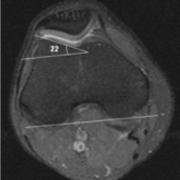

This patient's trochlear inclination angle is 22 degrees, which is in the normal range.

The LTI is an MRI calculation of the angle between the lateral edge of the femoral notch and the posterior edge of the femur at the level of the femoral epicondyles.

To measure the angle, one draws the line along of the wall of the trochlear groove underneath the cartilage layer. Then a line is drawn at the back of the two condyles - from it a parallel line can be extrapolated to meet the first one, to make it easier to see the angle.

If the LTI is 20-22 degrees the slope of the wall of the trochlea is considered normal. However, if it is below 11 degrees it is considered dysplastic. For some severely affected people it can be even zero or less. A flattened dysplastic trochlea makes it easier for a patella to sublux or to dislocate, and thus this angle is important to calculate when assessing the causes of such patellar instability.